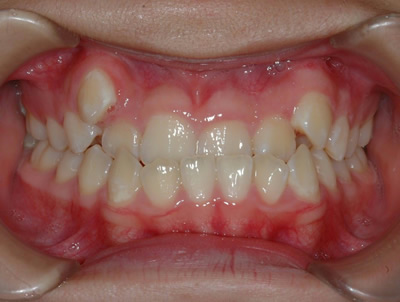

上顎の劣成長 (成長不足) による反対咬合で、上顎は拡大装置と上顎前方牽引装置を併用し前方方向への成長を促して前歯の咬み合わせを改善した後に、上下顎の前歯をマルチブラケット装置で並べました。治療の期間は2年でした。

初診時

1期治療終了時

2期治療終了時